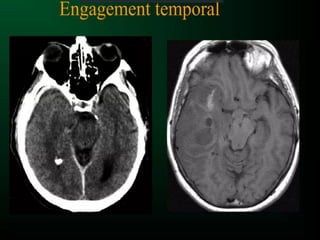

• Engagement cérébral : hernie de tissu

cérébral au travers des orifices naturels de

l’encéphale

ETAGE SOUS-TENTORIELLE

ETAGE SUS-TENTORIELLE

LE PLUS IMPORTANT !!